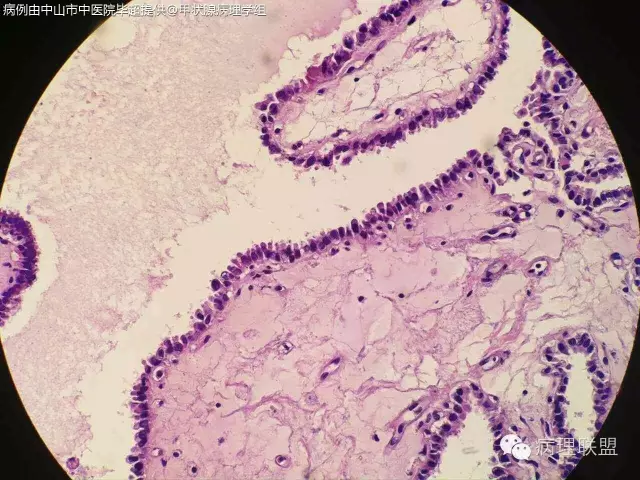

打脸病例分享,52/F,19年前因右侧甲状腺腺瘤行局部切除,因甲状旁腺功能亢进行甲状旁腺摘除,术中送检部分右侧甲状腺组织,冰冻切片未见异常,常规石蜡切片见乳头状结构,乳头间质见沙粒体,镜下图片如下:

自己在镜下看了半天核是有点挤,我们苏木素染色有点深,没看出有啥核沟和包涵体。因为出现沙粒体,上级医生不放心,加做免疫组化:

微小乳头状癌。这种结构有时看不到典型的核的特点。@毕超

@阳宇 我之前还觉得没有核特征不能下癌,这例的不典型是否和冰冻有关?我们染色有点深

嗯嗯。个人觉得跟冰冻有些关系,还待其他老师高见

PTC.核已经出现拥挤参差不齐,卵圆形有异性,加上沙立体的出现标准已够。实际上出现沙立体意味着PTC.但是要区分滤泡腔内深染浓缩的胶质。还有PTC强调在正常滤泡背景中的突然性,两者不能有移形。